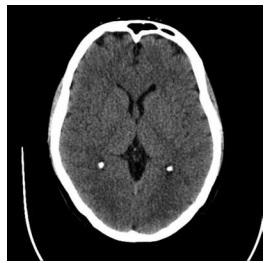

Homem de 62 anos, com histórico de hipertensão e diabetes mellitus tipo 2, é admitido ao pronto-socorro após episódio convulsivo tônico-clônico generalizado que não cessou espontaneamente. No hospital, ele apresenta um novo episódio, seguido por estado de consciência alterada sem recuperação entre os eventos. Sua glicemia capilar está dentro dos limites normais. O paciente é diagnosticado com status epiléptico convulsivo. Após administração de 20 mg de diazepam intravenoso e dose de fenitoína (20 mg/kg), as crises persistem. O EEG confirma atividade ictal contínua. TC de crânio inicial a seguir.

Enunciado 4448967-1 (https://www.google.com/url?sa=i&url=https%3A%2F%2Fradiopaedia. org%2Fcases%2Fnormal-ct-brain&psig=AOvVaw2r6xQdUHI-GJ_vfDIsQ9l0& ust=1734784743635000&source=images&cd=vfe&opi=89978449&ved=0CB QQjRxqFwoTCOidwPWutooDFQAAAAAdAAAAABAE)

Dada a progressão para status epiléptico refratário, a melhor próxima abordagem terapêutica é: